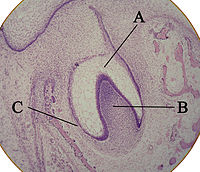

The first signs of an arrangement of cells in the tooth bud occur in the cap stage. A small group of ectomesenchymal cells stops producing extracellular substances, which results in an aggregation of these cells called the dental papilla. At this point, the tooth bud grows around the ectomesenchymal aggregation, taking on the appearance of a cap, and becomes the enamel (or dental) organ. A condensation of ectomesenchymal cells called the dental follicle surrounds the enamel organ and limits the dental papilla. Eventually, the enamel organ will produce enamel, the dental papilla will produce dentin and pulp, and the dental follicle will produce all the supporting structures of a tooth.

The tooth bud (sometimes called the tooth germ) is an aggregation of cells that eventually forms a tooth. These cells are derived from the ectoderm of the first branchial arch and the ectomesenchyme of the neural crest. The tooth bud is organized into three parts: the enamel organ, the dental papilla and the dental follicle.

The enamel organ is composed of the outer enamel epithelium, inner enamel epithelium, stellate reticulum and stratum intermedium. These cells give rise to ameloblasts, which produce enamel and the reduced enamel epithelium. The location where the outer enamel epithelium and inner enamel epithelium join is called the cervical loop. The growth of cervical loop cells into the deeper tissues forms Hertwig's Epithelial Root Sheath, which determines the root shape of the tooth.

The dental papilla contains cells that develop into odontoblasts, which are dentin-forming cells. Additionally, the junction between the dental papilla and inner enamel epithelium determines the crown shape of a tooth. Mesenchymal cells within the dental papilla are responsible for formation of tooth pulp.

The dental follicle gives rise to three important entities: cementoblasts, osteoblasts, and fibroblasts. Cementoblasts form the cementum of a tooth. Osteoblasts give rise to the alveolar bone around the roots of teeth. Fibroblasts develop the periodontal ligaments which connect teeth to the alveolar bone through cementum.